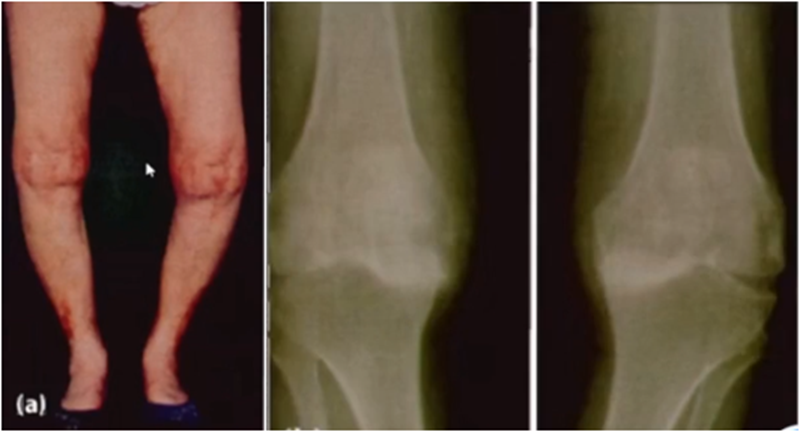

三、单髁置换的适应证——标准侧位片

标准侧位片,内外髁完全重叠,胫骨平台也一样,如果检查不标准,X线片结果会影响判断。

侧位片可以显示胫骨平台磨损部位,在判断前交叉韧带功能是否完好方面有重要意义。当磨损部位在前方或中前方,没有延伸到胫骨平台后缘时,说明前交叉韧带功能正常;当磨损部位延伸到胫骨平台后方,甚至引起后方半脱位状态时,说明前交叉韧带功能缺失或损害,此时不适合做单髁。

查体特点:屈曲位畸形消失

后方软骨完好,恢复关节间隙,恢复MCL张力

AMOA的侧位X线表现

ACL功能完好是单髁重要的适应证。当ACL失去功能,导致后方软骨磨损或者骨缺损,此时为整个内侧或全间室的骨关节炎,不是单髁的适应证了。

在牛津单髁标准教程里,表明前交叉韧带与后交叉韧带都应该保持功能正常,才是单髁的适应证。